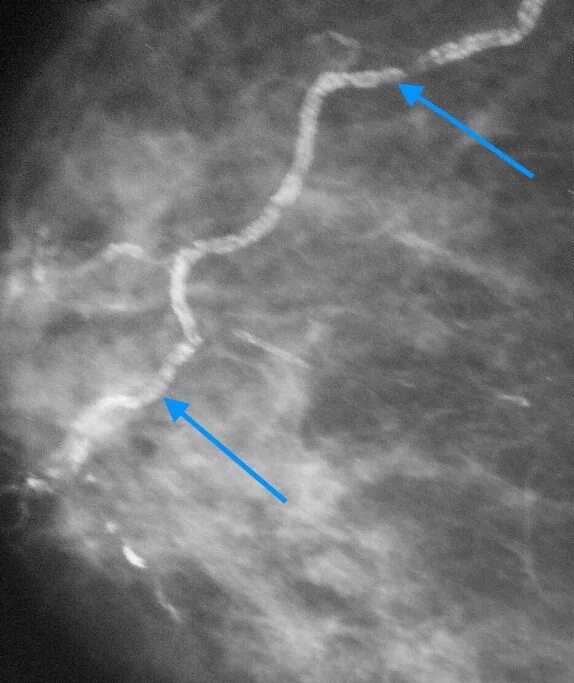

Кальцинация сосудов